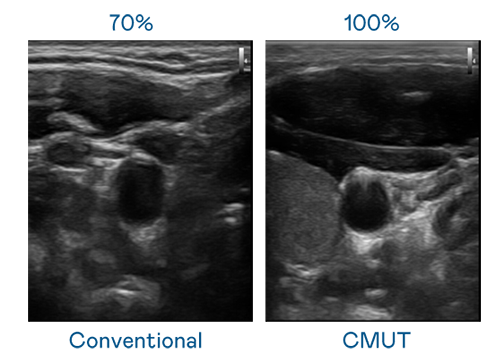

CMUT 技术是一种用电容式微机电元件来产生超音波讯号的技术。与传统 PZT 压电式技术相比,CMUT 频宽增加 30%,更宽频的超音波讯号让影像解析度大幅提升,是实现高影像品质医疗超音波扫描、促进精准医疗发展的关键技术。

大频宽带来超清晰影像

超音波影像的解析度高低,首先取决于探头能发出的讯号频宽。DB视讯 CMUT 可提供高清晰的超音波讯号,提供高频宽、高灵敏度、影像纹理细节更高的超音波影像,协助医护人员缩短影像判读时间及利用精准的医疗影像进行诊断。